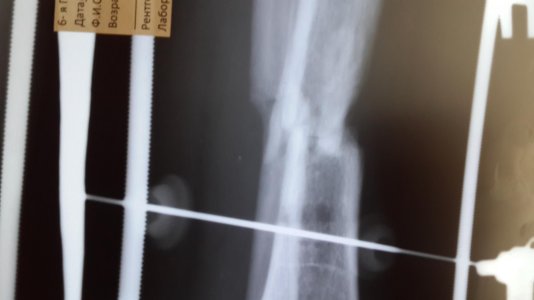

Здравствуйте доктор мне 26 лет , 29 июля 2016 года я получил травму на соревнования открытый перлом голени бб и мб кости , 12 августа поставили аппарат илизарова , 12 ноября сдела снимок костная мозоль слабая нормально ли это? с 16 ноября начал наступать на ногу даю вес 30кг , до этого не наступал

добавил снимки сделанные 29сентября и 12 ноября